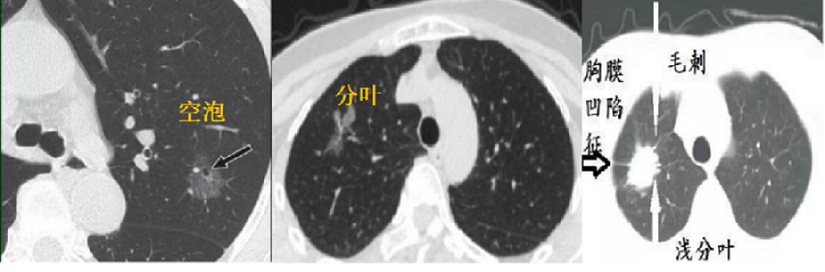

3、病灶形态。空泡型GGO、有分叶或毛刺、胸膜凹陷、血管集束及支气管充气等征象时恶性可能性大。

图五 恶性病灶影像学表现